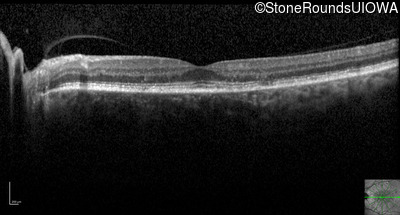

Optical Coherence Tomography - Left - 20/30

Exemplar / OCT Stack

Infrared Fundus Photograph - Left - 20/30

Exemplar